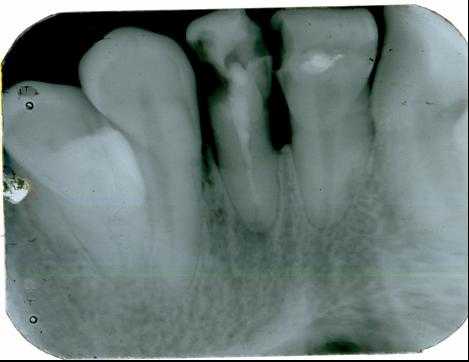

Признаком наличия кистозной полости является образование округлой или овальной формы достаточно однородной структуры с четкими ровными контурами. При лучевой диагностике радикулярной кисты удается проследить связь кистозной полости с верхушкой

корня зуба. Нередко корень зуба проникает в полость кисты. В структуре фолликулярной кисты всегда определяется коронковая часть непрорезавшегося, как правило, полностью сформированного зуба. На рентгенограммах изучаются такие симптомы: форма и размер кистозной полости, локализация, состояние кортикальных пластин челюсти, однородность структуры, наличие внутриполостных перегородок, степень деструкции костей и состояние зубов в проекции кисты. Контактные внутриротовые рентгенограммы обладают достаточной информативностью для определения кист небольших размеров и оценки состояния пародонта. При кистах больших размеров они не дают полной информации о рентгенологических признаках, а что особенно важно, не позволяют в полной мере оценить окружающие области, например верхнечелюстной синус. На рентгенограмме происходит суммация теней различных образований челюстно-лицевой области, что создает трудности при изучении рентгенограмм Радиовизиография с последующим компьютерным анализом оптической плотности изображения является диагностически значимым методом для оценки плотности костной ткани. Ее проводят для контроля процесса остеорегенерации в области костного дефекта после оперативного вмешательства.